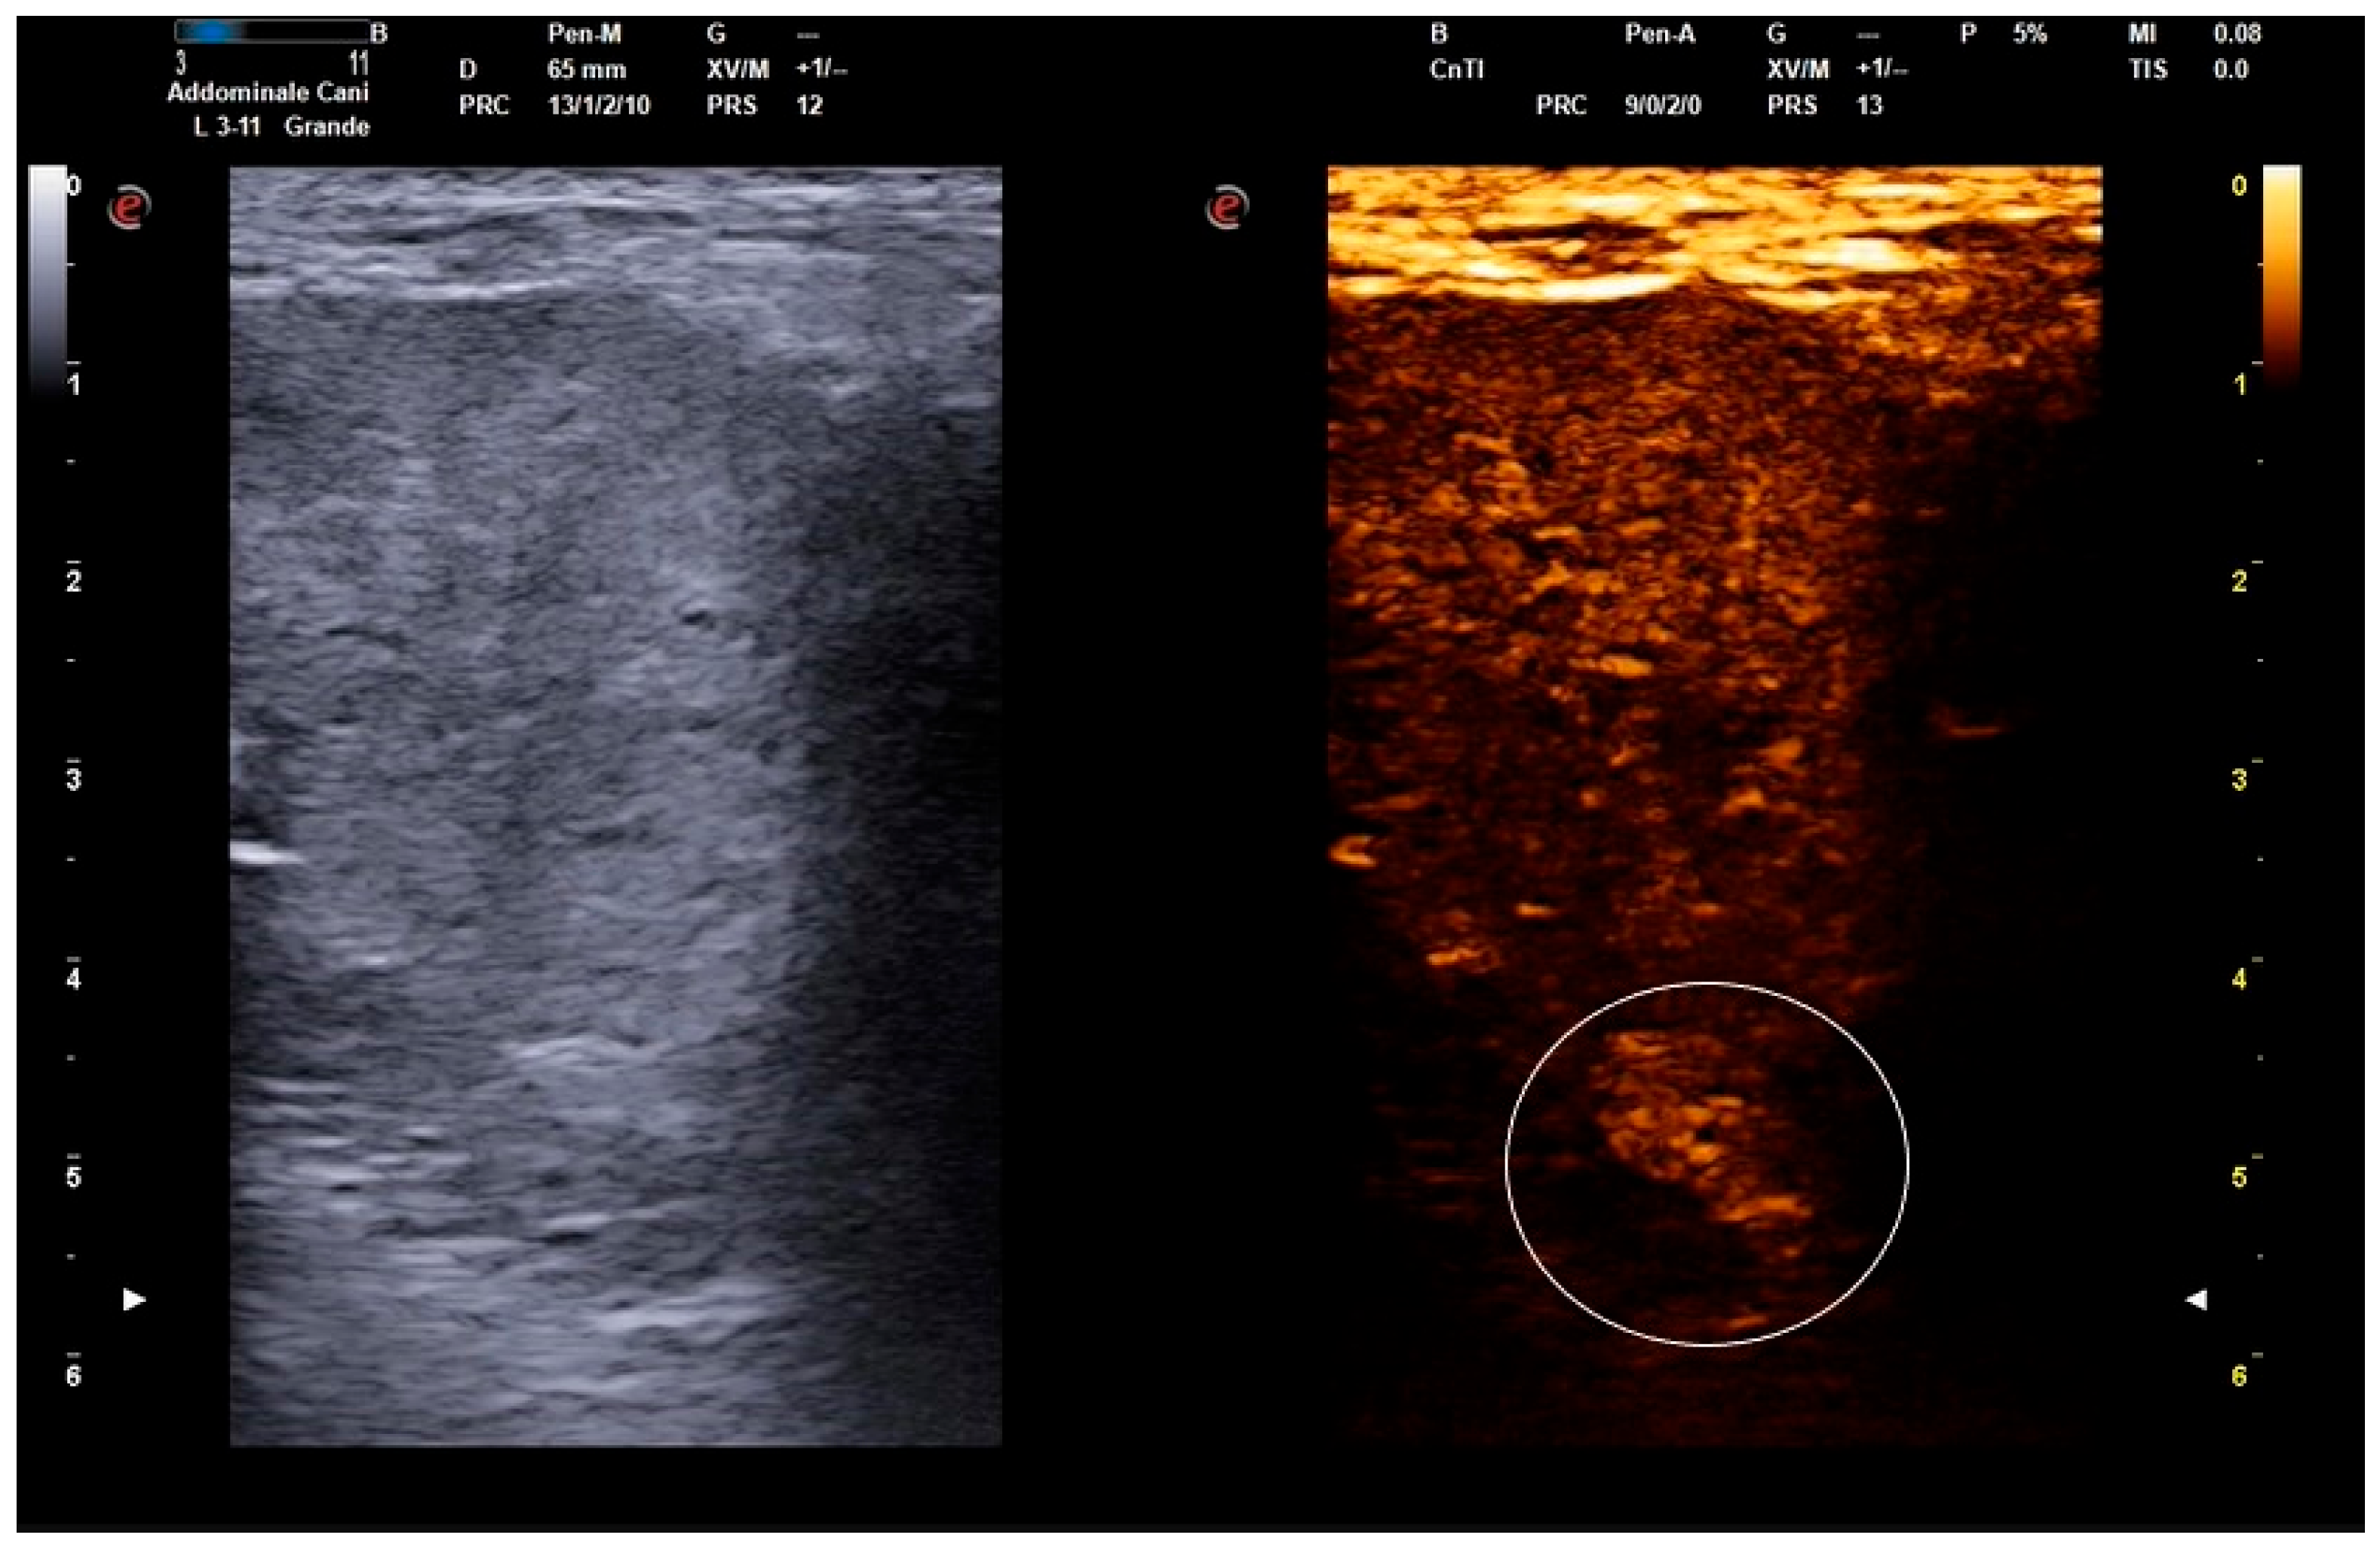

2.2. B-Mode and Contrast-Enhanced Ultrasound Procedures

- Russo, M.; Vignoli, M.; England, G.C.W. B-mode and contrast-enhanced ultrasonographic findings in canine prostatic disorders. Reprod. Domest. Anim. 2012, 47, 238–242. [Google Scholar] [CrossRef] [PubMed]

- Troisi, A.; Orlandi, R.; Bargellini, P.; Menchetti, L.; Borges, P.; Zelli, R.; Polisca, A. Contrast-enhanced ultrasonographic characteristics of the diseased canine prostate gland. Theriogenology 2015, 84, 1423–1430. [Google Scholar] [CrossRef] [PubMed]

- Russo, M.; Vignoli, M.; Catone, G.; Rossi, F.; Attanasi, G.; England, G.C. Prostatic perfusion in the dog using contrast-enhanced Doppler ultrasound. Reprod. Domest. Anim. 2009, 44, 334–335. [Google Scholar] [CrossRef]

- Bigliardi, E.; Ferrari, L. Contrast-enhanced ultrasound of the normal canine prostate gland. Vet. Radiol. Ultrasound 2011, 52, 107–110. [Google Scholar] [CrossRef]

- Vignoli, M.; Russo, M.; Catone, G.; Rossi, F.; Attanasi, G.; Terragni, R.; Saunders, J.; England, G.C. Assessment of vascular perfusion kinetics using contrast-enhanced ultrasound for the diagnosis of prostatic disease in dogs. Reprod. Domest. Anim. 2011, 46, 209–213. [Google Scholar] [CrossRef] [PubMed]

| Wash-in (s) | 11.93 ± 2.08 (8–16) | 14.73 ± 2.54 (10–21) | <0.001 |

| Wash-out (s) | 42.20 ± 6.99 (35–60) | 51.13 ± 6.03 (46–65) | <0.001 |